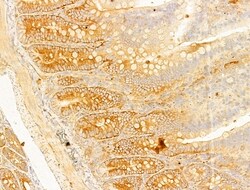

| Immunocytochemistry, Immunohistochemistry (Paraffin), Western Blot | |